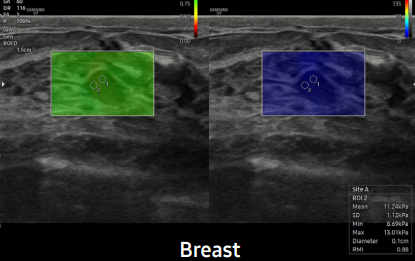

Exquisita calidad de imagen para una mayor fiabilidad y confianza

Mejore su apreciación sobre la evaluación del problema basado en un rendimiento de imagen excepcional impulsado por el motor de imagen principal de Samsung, Crystal Architecture™. El motor de imagen premium combina las ventajas del procesamiento de imágenes 2D mejorado y la expresión detallada del procesamiento de la señal de color. El V7 proporcionará una calidad de imagen sobresaliente para un diagnóstico de confianza.